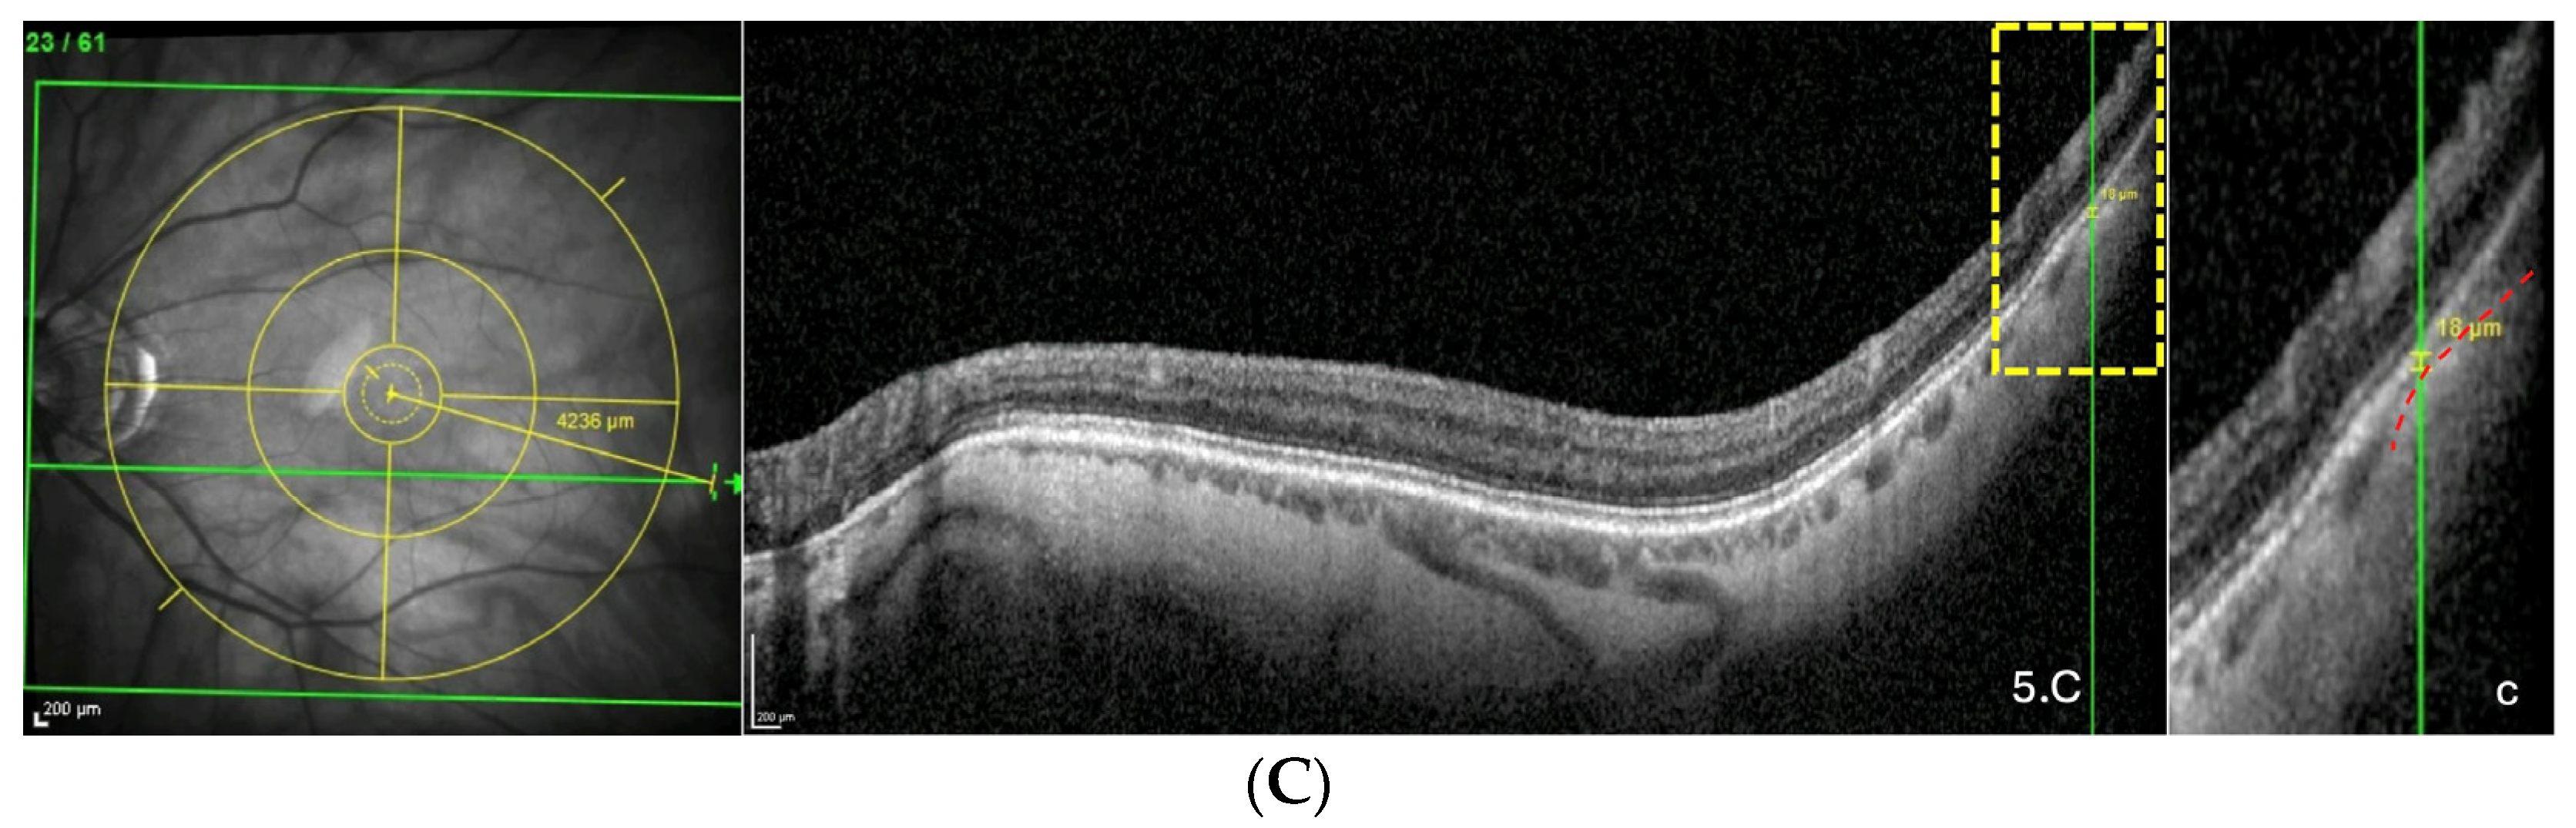

Based on OCT, a PS is defined by an outward protrusion of the sclera ending in an inward scleral deformation at its edges. In addition, the choroid thins towards the edge of the PS and re-thickens towards the outpouching of the PS [20,21].

The thinning of the choroid due to compressive force applied to the sclera has been previously documented [8,22]. This thinning is followed by a re-thickening at the limits of the compressed zone. It has also been suggested that the choroid thickens where the sclera is pulled outward [4,5,13] because Bruch’s membrane, thanks to its resistance, tends to maintain its plane [23].

From this, it was suggested that the underlying pathogenesis of some forms of PS involves inward scleral deformation by compression forces and its outward deformation by traction forces [4,5,13] applied by ON sheaths [4,5] or oblique muscles [13]. The repetition of these deformations over time would lead to a remodeling and fixation of the tissues in the deformed configuration [4,5,13] (Figure 7).

Figure 7.

Illustration of two choroidal thinnings related to scleral inward deformations. The choroidal thinning at the peripapillary zone (red arrow) would result from squeezing by the optic nerve sheaths, while the other thinning, temporal to the macular position (yellow arrow), would be related to the action of the inferior oblique muscle.